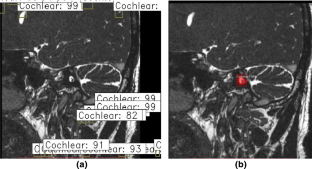

The main scope of this research is to present an automatic method to detect and segment the IAC and its nerves like the facial nerve, cochlear nerve, inferior vestibular nerve, and superior vestibular nerve. To address this issue, we propose a Mask R-CNN approach driven with U-net to detect and segment the IAC and its nerves. The Mask R-CNN with its backbone network of the RESNET50 model learns a background-based localization policy to produce an actual bounding box of the IAC. Furthermore, the U-net segments the structure related information of IAC and its nerves by learning its features.

The proposed method was experimented on clinical datasets of 50 different patients including adults and children. The localization of IAC using Mask R-CNN was evaluated using Intersection of Union (IoU), and segmentation of IAC and its nerves was evaluated using Dice similarity coefficient.

The localization result shows that mean IoU of RESNET50, RESNET101 are 0.79 and 0.74, respectively. The Dice similarity coefficient of IAC and its nerves using region growing, PSO and U-net method scored 92%, 94%, and 96%, respectively. The result shows that the proposed method outperform better in localization and segmentation of IAC and its nerves. Thus, AI aids the radiologists in making the right decisions as the localization and segmentation of IAC is accurate.